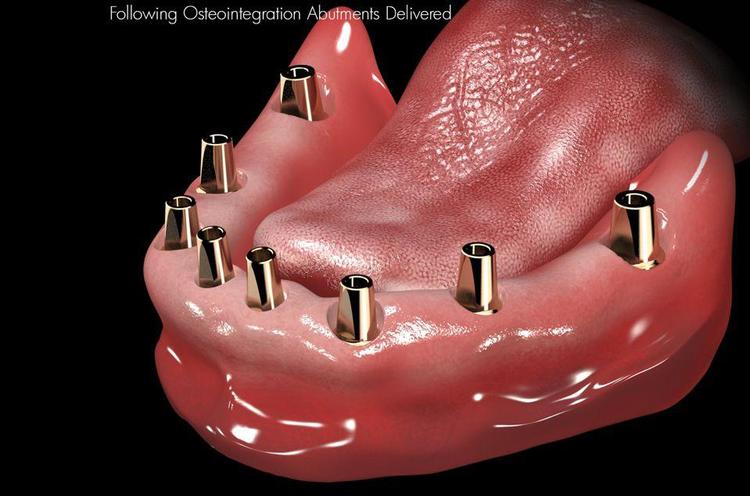

诚和植牙優勢

1. 最新3D高科技醫療設備

本院设备最新植牙專用3D (CBCT) 体影像設備,可決定最佳的植入位置 角度,大幅度提高植牙的安全性, 成 率, 與準確度。

2. 植體材料優勢

本診所採用的是美國頂級FDA標準的植牙系統, 卓越的初期穩定性, 親骨性強, 癒合最快。

3. 微創植牙技術

疼痛程度低,傷口小且快速的植牙技術。

4. NYU 大學植牙醫師為您診治

本院植牙專師陳賜恆醫師具多張植牙證照與專利 ,包括紐約大學植牙部門的Implant Fellowship,能讓您安心與放心。 經驗豐富, 超過數千個成功案例; 接近100%成功率。

全口植牙的優點包含了:

1. 假牙穩定性高,不易鬆脫。

2. 支撐效果好,不易造成牙床破皮。

3. 咀嚼功能佳,一般稍硬食物均可化解。

4. 假牙體積減小,降低口腔不適感。

5. 重建後使用滿意度高。

6.当天种,当天用! 多颗人工牙根植入后,可以直接当天在上面安装固定假牙, 且不会影响种植牙的使用寿命。

真实病例